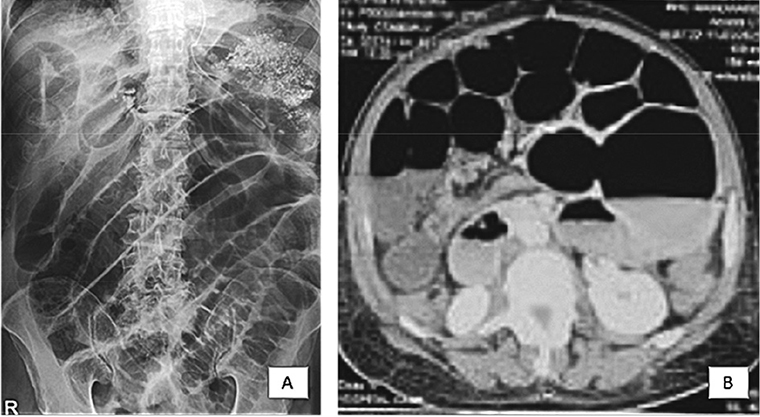

On X-ray abdomen erect and supine with both domes of diaphragm multiple air fluid levels were seen suggestive of intestinal obstruction. There was no gas under diaphragm (Figure 1A).

Vipin-1.tif

Figure 1. A, B

Underwent CECT abdomen on suspicion of small bowel obstruction. The finding were suggestive of small bowel obstruction with a definitive transition zone at distal ileum and four centimetre dilatation of proximal small bowel loops (Figure 1B).